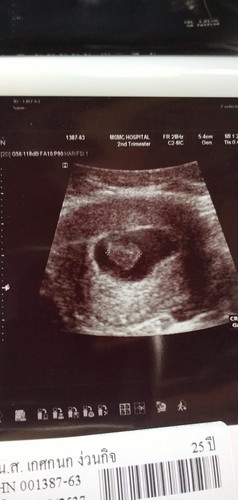

ผลการอัลตร้าซาวด์ดูหัวใจเด็กเต้น แต่ไม่เจอ มี 2 กรณี 1.ตัวเด็กในครรภ์ยังเล็กจึงมองไม่ให้ 2. อาจจะมีอัตรายกับเด็ก

ของเราเลือดออกตอน7wคะ แต่เจอน้องนะมีหัวใจ หมอบอกอาจจะเป็นแท้งคุกคามหมอให้ฉีดยากันแท้งคะ พอ10wเลือดไหลเป็นทางเลยคะ หมอซาวดูโชคดีมากน้องไม่เป็นอะไร หมอสรุปเป็นแท้งคุกคามให้นอนเฉยๆอย่าทำอะไร และฉีดยากันแท้งอีกเข็ม ตอนนี้13wแล้วคะ สู้ๆนะคะแม่อย่าทำงานหนักนะคะ

เราเคยซาวครั้งแรก 5w ทางหน้าท้องไม่ได้ยินเสียงหัวใจ ต่อมาเรามีเลือดออกตอน 6w หมอเลยซาวผ่านทางช่องคลอดให้ ได้ยินเสียงหัวใจน้องชัดเจนค่ะ ถ้ามีเลือดออกรีบไปหาหมอก่อนหมอนัดก็ได้นะคะ